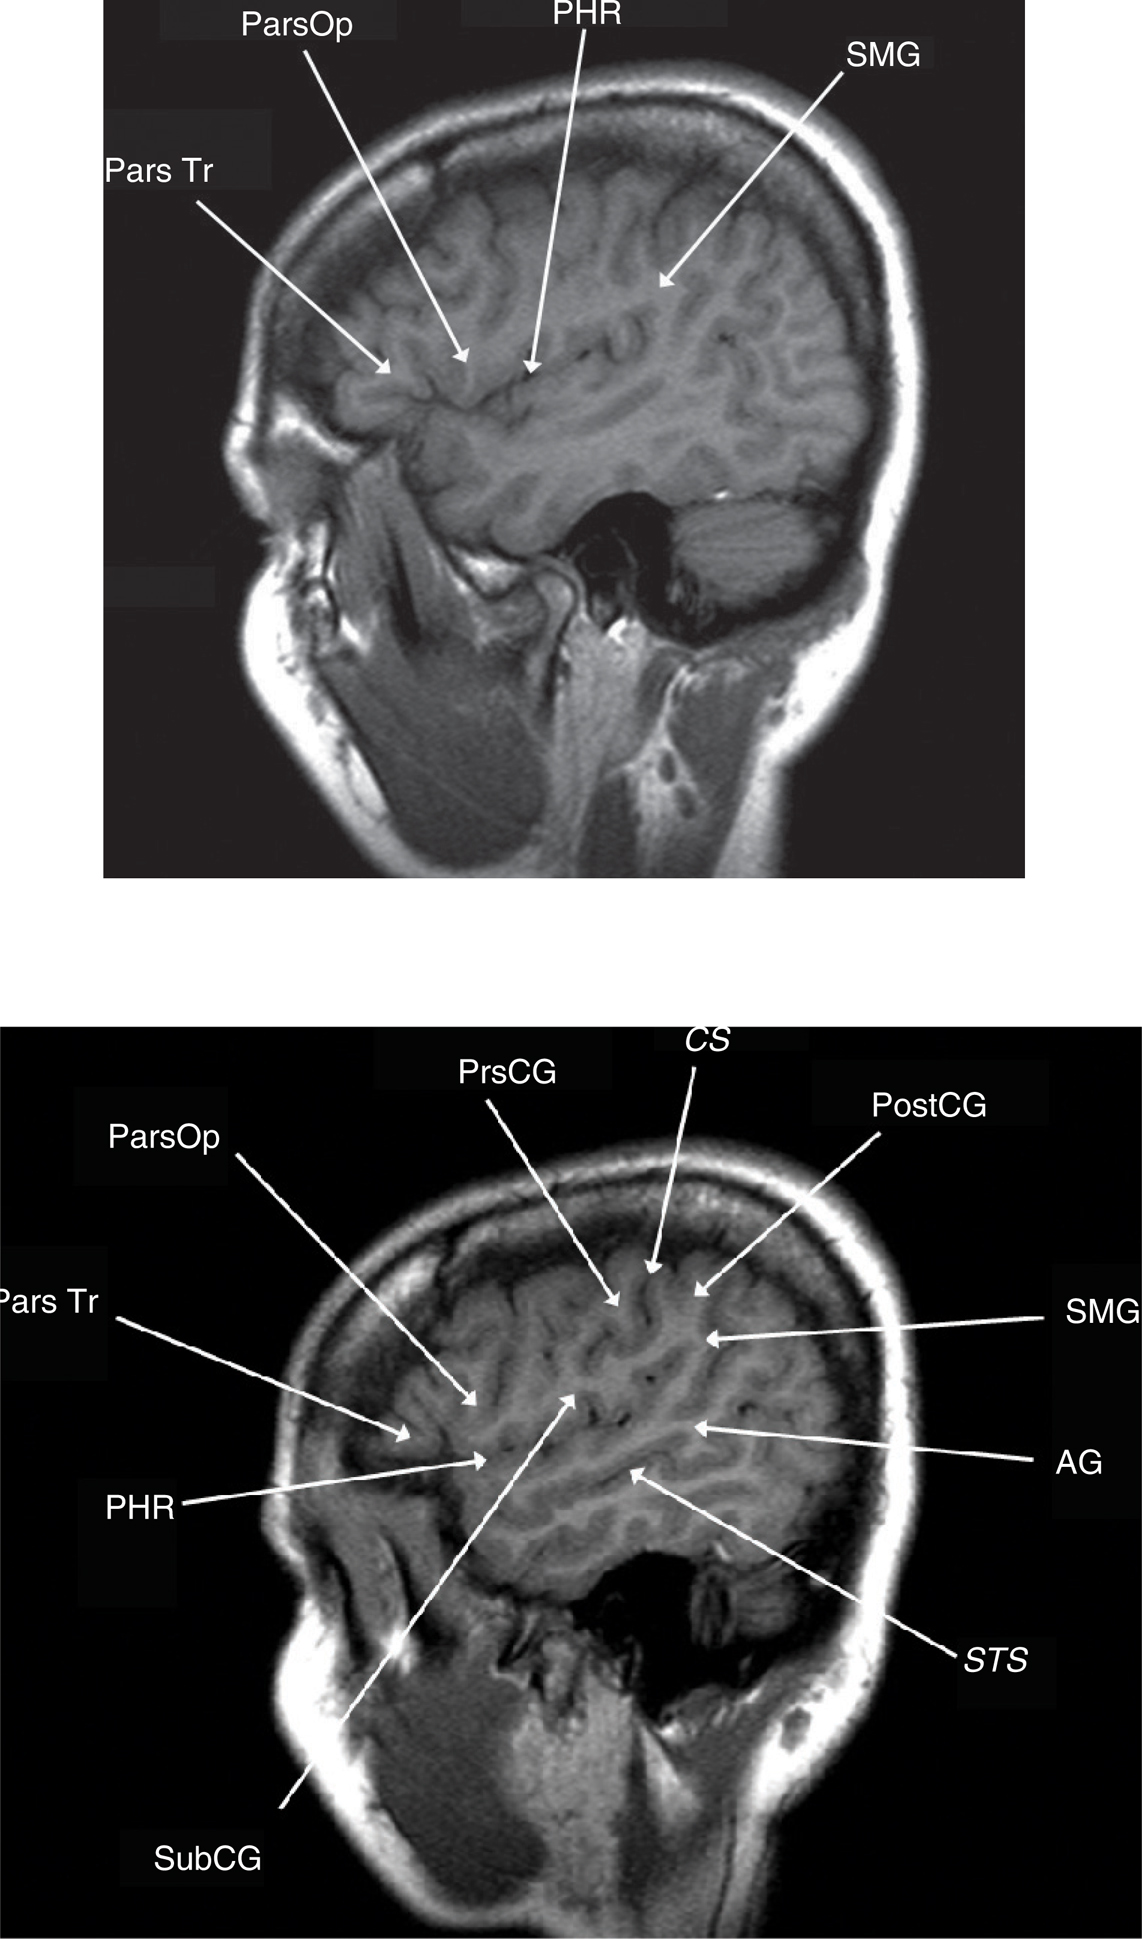

The frontal lobe contains three gyri (superior, middle, inferior) separated by the superior and inferior frontal sulci. The superior frontal gyrus is appreciated on both axial and sagittal images (Figure 1). The middle frontal gyrus (MFG) extends posteriorly and fuses with the vertically oriented precentral gyrus. The precentral sulcus starts at midline and extends anteriorly and laterally in an oblique direction. The next key finding is the merging of the inferior frontal sulcus with the inferior ramus of the precentral sulcus, forming a “T” shape (4, 5). More posteriorly, the central sulcus is identified over the convexity on axial or sagittal images. It is oriented obliquely from posterior to anterior and does not extend all the way into the Sylvian fissure. Inferiorly, the precentral gyrus and postcentral gyrus merge under the central sulcus through a “U”-shaped gyrus (the subcentral gyrus). The post-central gyrus is characteristically narrower than the precentral gyrus (4, 5). Posteriorly, the Sylvian fissure is capped by the SMG, which is the anterior most portion of the inferior parietal lobule. Inferiorly, within the temporal lobe, coursing in parallel with the Sylvian fissure, is the superior temporal sulcus, which is capped posteriorly by the angular gyrus, the posterior limit of the inferior parietal lobule. The angular gyrus (Brodmann’s area 39) and posterior aspect of the superior temporal gyrus (STG) (Brodmann’s area 22) represent the primary receptive speech area (Wernicke’s area). The SMG (Brodmann’s area 40) contains fibers from the arcuate fasciculus that connect Wernicke’s and Broca’s areas (4, 5). The cingulate sulcus separates the cingulate gyrus from the medial aspect of the superior frontal gyrus. If followed posteriorly, the cingulate sulcus angles superiorly to form the pars marginalis, marking the posterior aspect of the paracentral lobule. The paracentral lobule houses the central sulcus, Broadman Areas 3,1,2 and 4,6. On axial images, the pars marginalis may be appreciated as a “bracket” (pars bracket) extending symmetrically from midline left and right. Anterior to this are the primary motor cortex and the postcentral sulcus. Areas 3,1,2 relate to the primary sensory cortex, and areas 4,6 include primary motor and supplemental motor areas (4, 5) (Figures 1 and 2).

Fig 1

Figure 1 Axial T2-weighted MRI showing the middle frontal gyrus (MFG), superior frontal gyrus (SFG), superior frontal sulcus (SFS), central sulcus (CS), supplementary motor area (SMA), postcentral sulcus (PCS), pars bracket (PB), hand motor area (HMA), and proximal leg area (PLE).